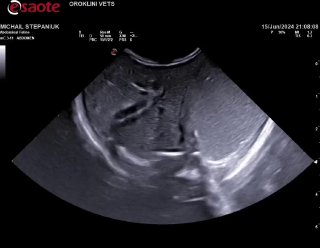

Нарушена перистальтика скорее всего, дело не в Кале, молоко не переходит из желудка дальше, а выходит обратно… надо узи. В ороклини пообещали принять, но уже 6:30, с 2 жду((( никто не пришел туда

Заворот желудка тоже может быть. На практике был один малыш,ему было пара недель вроде,заворот,оперировали и удачно,вырос в большого котэ🐈